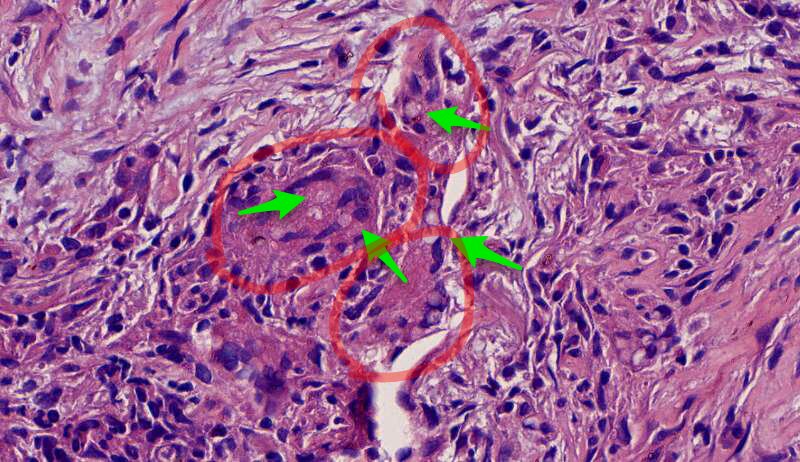

蓝色圈圈是菌丝团?红色箭头是淋巴细胞?这是空腔边缘吗?王:是的,红箭头也可能是中性粒细胞。 红箭是支气管粘膜有炎症。

这里的菌丝形态清楚,下图小圆空的结构挺多,我理解为管状菌丝的断面